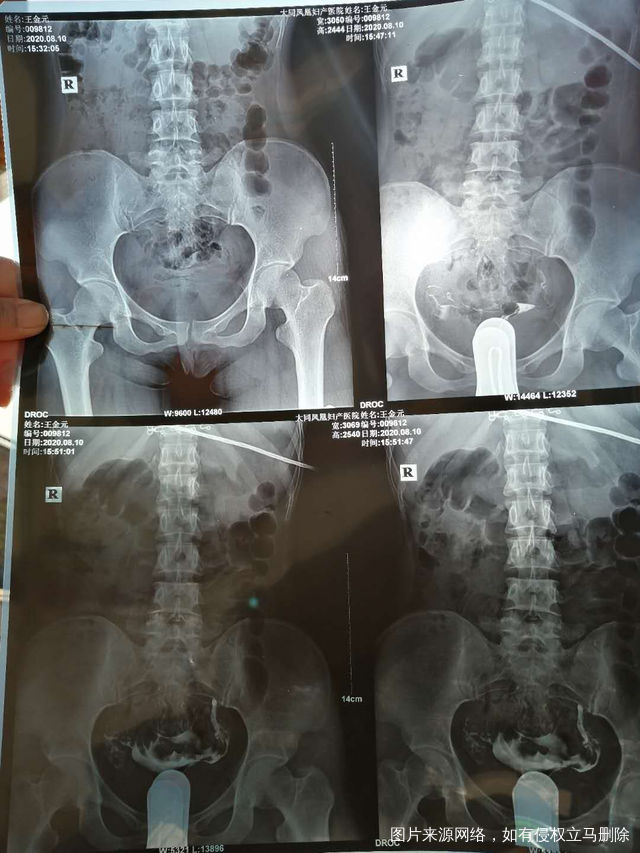

照影的结果是一边通而不畅一边显影并上举请问医